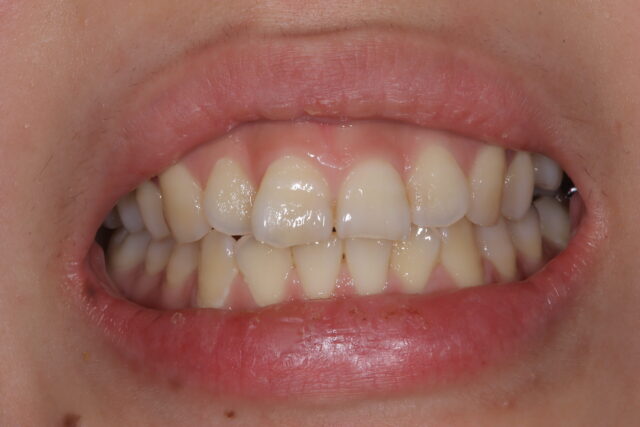

After

ガミースマイル治療Before After

たった2時間でガミースマイルが治りました!リップリポジショニングの場合、最短1回のご来院で治療できます。